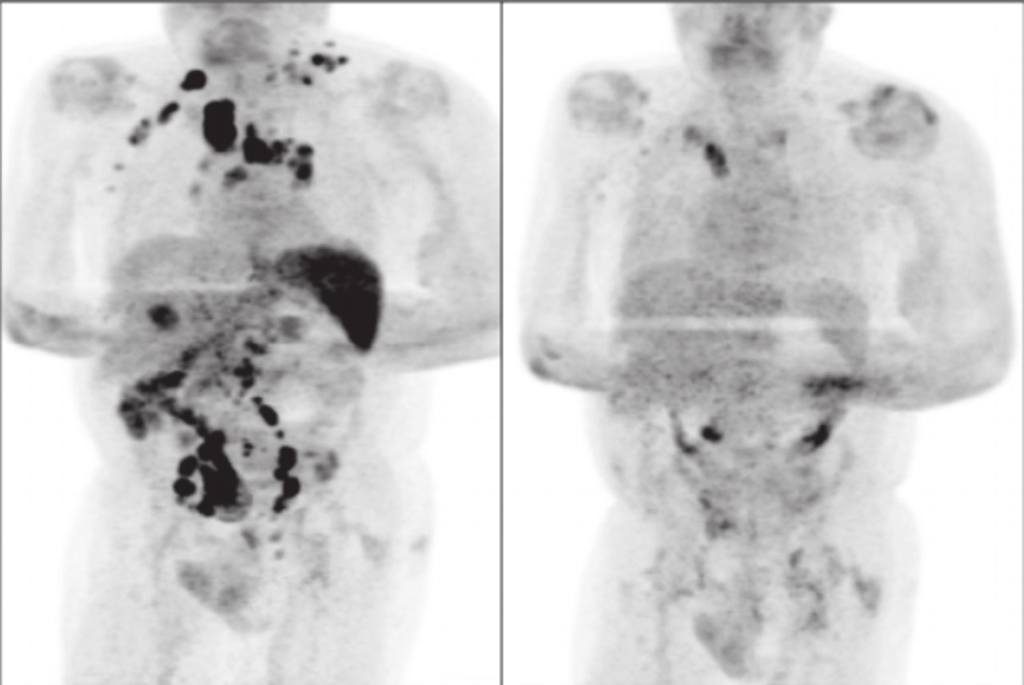

《英國血液學雜誌》(British Journal of Haematology)近日發表臨床病例報告,1名患腎衰竭

的61歲英國男子移植腎臟失敗後,3年來沒再接受免疫抑制治療。早前男子因體重銳減及淋巴結腫大

被送往醫院血液科檢查,確診霍奇金氏淋巴瘤(Hodgkin's lymphoma),癌細胞更已擴散至全身。

英國男子之後再因呼吸困難及氣促入院,不幸再被驗出對新冠病毒呈陽性反應,經過11日治療後出院。

在家休養期間,英國男子沒有獲處方免疫療法或皮質類固醇藥物。4個月後,醫護人員為男子進行

斷層掃描,竟發現他淋巴結腫大的情況有所減輕,體內腫瘤亦大規模消失,PCR腫瘤指數也大幅下降。